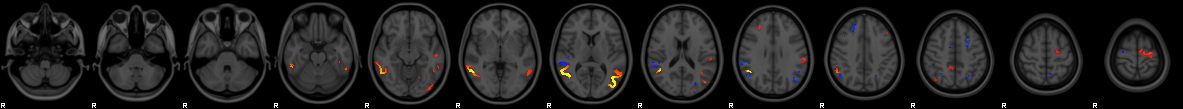

Modality Area (mi2) lightboxes